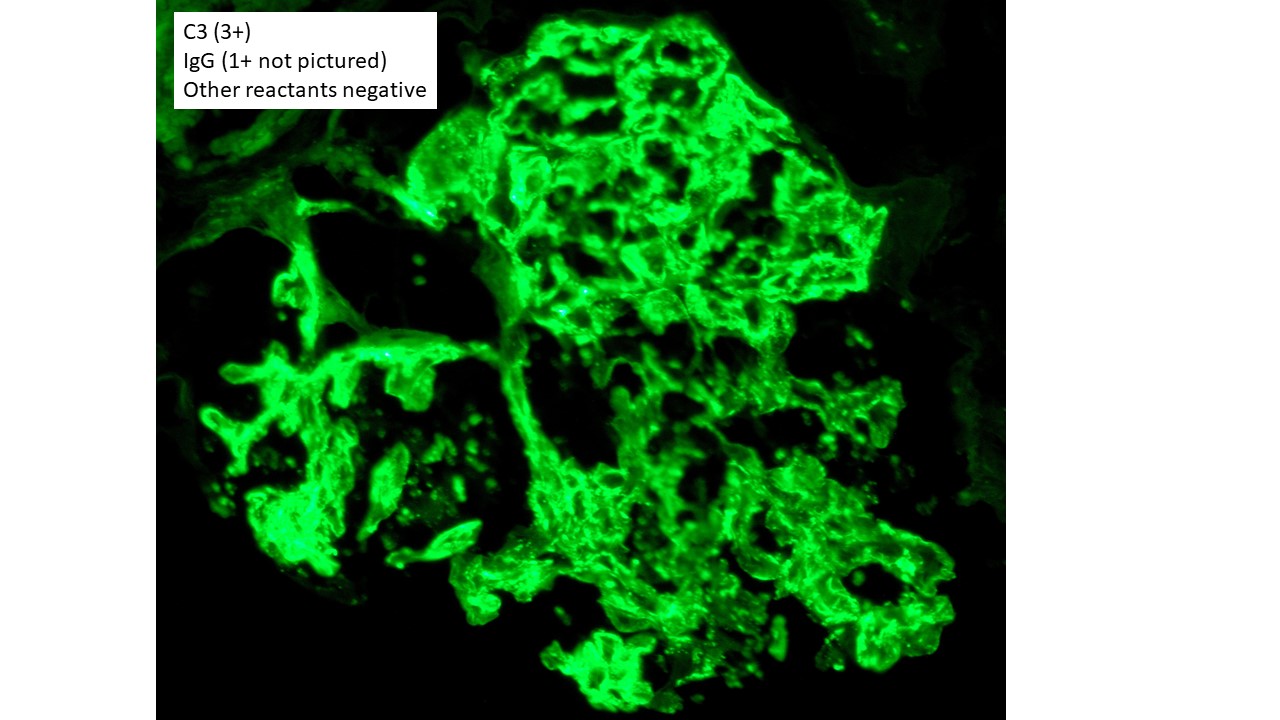

The findings in this patient’s renal biopsy are characteristic of acute postinfectious glomerulonephritis. Light microscopy shows a diffuse and global glomerular exudative process. Glomerular hypercellularity is primarily due to an influx of leukocytes (especially neutrophils, but also admixed monocytes), but which also includes a component of intrinsic renal cell proliferation (e.g. podocytes and mesangial cells), as well as endothelial cell swelling. Jones silver stain highlights the capillary basement membranes within glomerular tufts, and leukocytes and swollen endothelial cells can be seen filling and distend the glomerular capillary lumina. Immunofluorescence staining in this case showed predominant staining for C3 (3+ intensity), with lesser staining for IgG (1+ intensity) in a coarse chunky granular pattern that is mainly seen along capillary walls, often described as “lumpy bumpy” or “starry sky”, indicating a predominantly subepithelial deposition of immunoreactants. Other immunoreactants were negative. Electron microscopy in this case was classic of postinfectious glomerulonephritis, with large “hump-like” electron dense deposits seen in the subepithelial location.